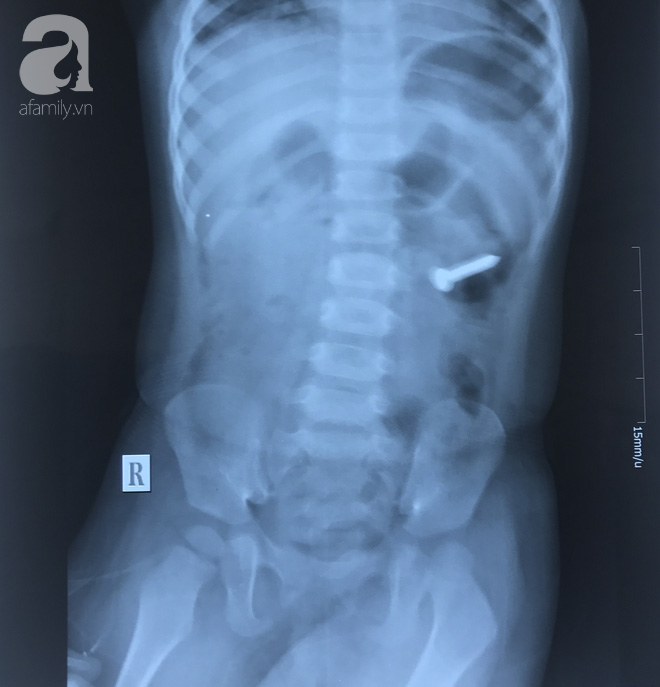

Qua thăm khám và chụp X – Quang, các bác sĩ phát hiện 1 dị vật cản quang trong dạ dày. Tiến hành hội chẩn, ekip điều trị quyết định nội soi gây mê để lấy dị vật ra. Gia đình cho biết, cháu bé chơi một chiếc đinh ốc xoắn và vô tình nuốt phải đinh .

Sáng 28/6, bác sĩ Phùng Thị Hằng, Trưởng khoa Nội của BV, người trực tiếp tiến hành thủ thuật cho biết, sau khi đặt máy, xác định được dị vật đã xuống sâu hơn. Do dị vật có bề mặt xoắn ốc lại dài 3cm so với kích thước lồng ruột của trẻ 2 tuổi nên thủ thuật tiến hành rất khó khăn.

Chiếc đinh xoắn ốc có chiều dài đến 3cm.